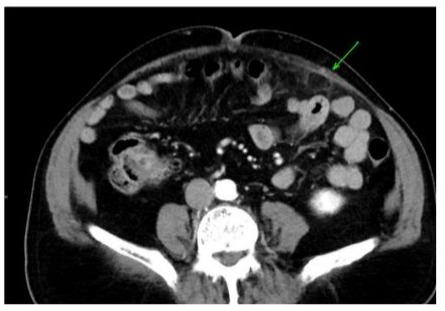

In the emergency department, a CT scan of the abdomen and pelvis revealed mild colonic diverticulosis without signs of acute diverticulitis and left mid-abdomen antimesenteric focal fat infiltration in the epiploic appendages. The figures below are CT scans of the transverse and coronal abdominal views, respectively, illustrating antimesenteric focal fat infiltration in the left mid-abdomen, which suggests EA (Figures 1 and 2). The scan also revealed right lower lobe pulmonary nodules measuring up to 0.6 cm, with a recommendation for chest CT follow-up in 6–12 months. Prominent vascular calcifications were evident in the aortoiliac arteries. A transthoracic echocardiogram (TTE) performed subsequently demonstrated a trileaflet aortic valve with reduced systolic excursion, moderate calcific aortic stenosis, and trace aortic regurgitation. The patient left the ED prior to receiving a formal diagnosis and was later informed of the findings by his internist.

Figure 2: Transverse view of EA pointing to left mid-abdomen antimesenteric focal fat infiltration.